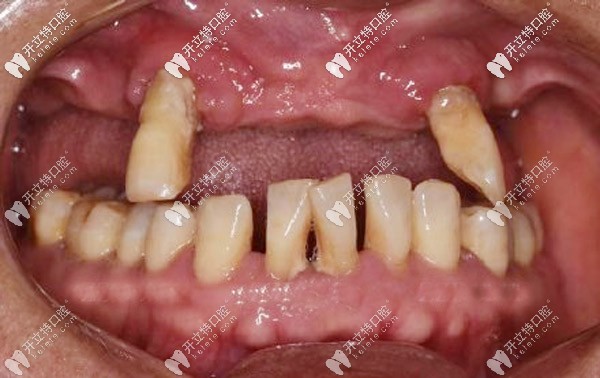

周老先生十多年前先后缺失了三四顆牙后鄰牙就開(kāi)始晃動(dòng),直到今年年初,上頜的牙齒只剩下兩顆,吃飯也受到影響才去牙科看牙。

“很多老人口腔情況跟我一樣,覺(jué)得掉牙不是什么事兒,即使旁邊的牙松動(dòng)了,也是能拖就拖,疼了就吃點(diǎn)消炎藥,誰(shuí)知道這樣一拖問(wèn)題”

周老先生后悔地說(shuō),自己年輕的時(shí)候就是太輕視缺牙,沒(méi)有及時(shí)修復(fù),才導(dǎo)致現(xiàn)在的牙齒松動(dòng),東西都得拿手掰著吃,根本不敢拿牙咬。

經(jīng)過(guò)口腔CT三維拍片確診,周老先生患有牙周炎,且有牙齦萎縮的情況。羅緣口腔的種植醫(yī)生通過(guò)數(shù)字化動(dòng)態(tài)導(dǎo)航系統(tǒng)在計(jì)算機(jī)上重建口腔頜骨三維立體模型。